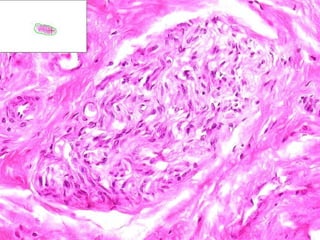

• #47 Schwannoma But really, could this be ANY soft tissue tumor?

• #48 Antoni A: Palisading, “Verocay” bodies Antoni B: Edema, “myxoid”